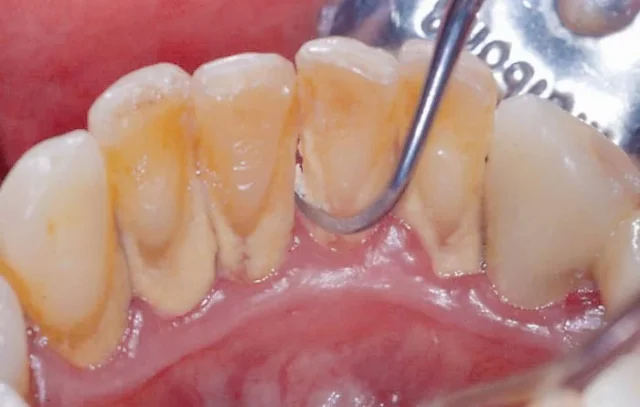

Trong quá trình lấy cao răng, đặc biệt là khi sử dụng các dụng cụ cạo siêu âm, có thể gây ra tổn thương cho mô mềm như nướu, má trong, lưỡi. Các tổn thương này thường biểu hiện bằng cảm giác ê buốt, chảy máu, sưng đau.

Quá trình lấy cao răng có thể gây ra tình trạng ê buốt răng, đặc biệt là ở những người có răng nhạy cảm hoặc men răng mỏng. Tình trạng này thường tự khỏi sau vài ngày, nhưng có thể gây khó chịu trong sinh hoạt hàng ngày.